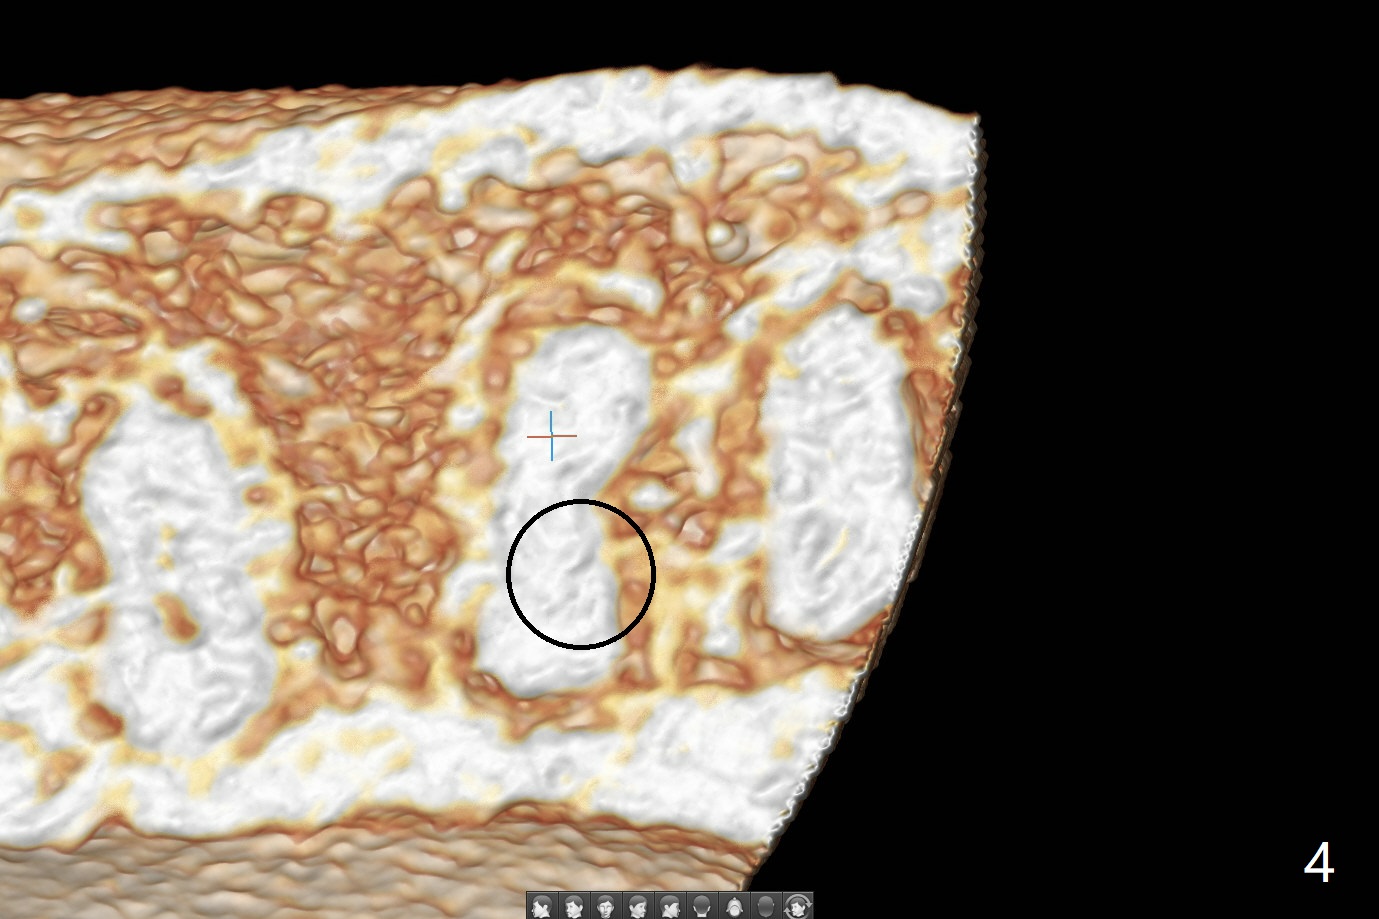

即刻种植即刻修复偶尔出现骨粉丧失,今天我们尝试临时基台,它可以制作像螺丝固位牙冠,可能会减少骨粉流失。左下7颊侧肿胀(图一:*),为了让植体(图二:绿色)植入中隔正中,钻洞时保留近中(M),远中(D)牙根。但是意想不到的是在导板指引下,钻头还是偏移近中(图三),而且颊侧(图四:圆圈),不过颊侧骨板没有缺损。由于牙根存在(硬),钻洞吃力,之后拔除,完成最后一个钻头,放置植体(图五),方位仿佛不错,临时基台(5.2x8(2)毫米)也完全就位,树脂围绕基台制作临时牙冠(图六),最后使用螺丝固位(*),颊侧肿胀牙龈必须用缝线固定(<),减少骨粉损失。由于牙冠与基台连接不好,病人汇报有些骨粉丢失。术后一个月检查尚可愈合正常,病人满意,已经做好思想准备做右下第二磨牙种植。临时牙冠进行修整。术后即刻近中牙槽窝间隙由粘性骨粉充填(图五),四个月后间隙消失(硬骨板也消失,图七),5.2x5(3)毫米粘固基台似乎没有完全就位,可能因为远中牙槽嵴阻挡(图七:*)。小一号基台仿佛完全就位(图八(咬翼片);图七(根尖片,可能失真)),但是临床上没有听到清脆声音(可能软硬组织阻挡)。随着时间推移,远中牙槽嵴吸收,当松动基台螺丝再次拧紧,可能会真正完全就位,必须拍摄完美咬翼片证实。这种植体芯(body, not threads)特别厚内部结构看不清楚。两周后粘固牙冠,然后取出牙冠和基台,清除残余粘固剂,然后复位,拧紧30Ncm。